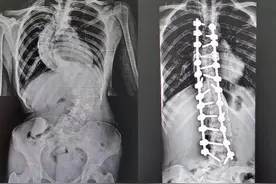

长沙晚报掌上长沙7月29日讯(全媒体记者 傅容容 通讯员 章茹)“9月开学,我可以自信地回到校园了!”今日,在湖南省第二人民医院脊柱外科,来自溆浦县的16岁女生小琳(化名)非常开心。被脊柱侧弯困扰多年的她,终于挺直了腰杆,“长高”6厘米。

暑假期间,来自溆浦县的小琳(化名)同学在湖南省第二人民医院“长高”了6厘米。今年16岁的小琳在4年前因为腰背部反复疼痛,在当地确诊为脊柱侧弯畸形。由于家庭条件限制,加上学业紧张,一直没有进行系统的治疗。疾病给小琳的生活蒙上了一层阴霾。

来源:【华声在线】华声在线7月30日讯(全媒体记者 李琪 通讯员 章茹 黄艳 张警盈 曾星怡)“还有一个月开学,我可以自信地回到校园啦!”7月30日,湖南省第二人民医院脊柱外科,来自怀化溆浦县的16岁女生罗小琳(化名)开心地说道。